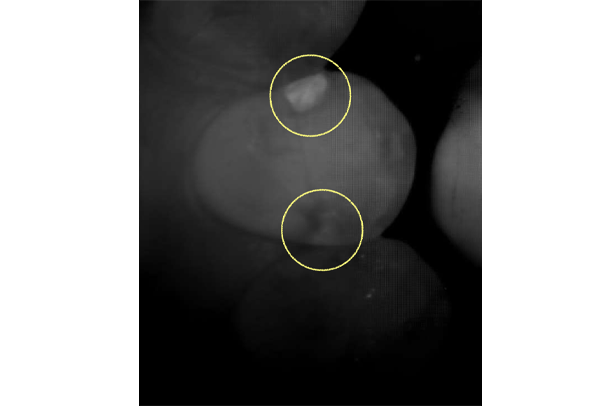

インレー症例

初診時パノラマ

初診時口腔内写真

iTero NIRI機能による診査

虫歯除去後

初診時バイトウィングデンタル

レントゲンだとちょっと虫歯が怪しいくらいに写っている。これだけだと確定診断としては、判断材料が少ないと考えられる。

黄色丸の部位が、他の部位と違って白く抜けがあるのがわかります。これがNIRI機能による虫歯の診査です。

この機能のおかげで、歯と歯の間の見つけにくい虫歯がよくわかるようになってきました。

In(インレー)セット後

年齢・性別 40代・男性

主訴 左上の奥歯がしみることがある

治療内容 左上4の虫歯

治療期間 2週間

リスク・副作用 虫歯の大きさによっては、神経をとらないといけなくなることがあります。

また、虫歯が大きかったケースで神経を残した場合、治療後にしみるなどの

症状が続くことがあります。

費用 ・ジルコニアインレーで修復

55,000円

治療方針

IOSのNIRI機能によって虫歯部分が明らかになったので、虫歯を除去後に修復治療を行うこととしました。

担当医師所見

虫歯の有無を確認する上で今まではレントゲンと自分の目での確認でした。現在は目で見るよりもはるかにわかりやすいIOSという装置がありますので、虫歯の発見がしやすくなりました。

そのため、患者さんの虫歯の進行の段階が早いうちにわかる様になり、神経をとらなければならないというケースが非常に少なくなっています。